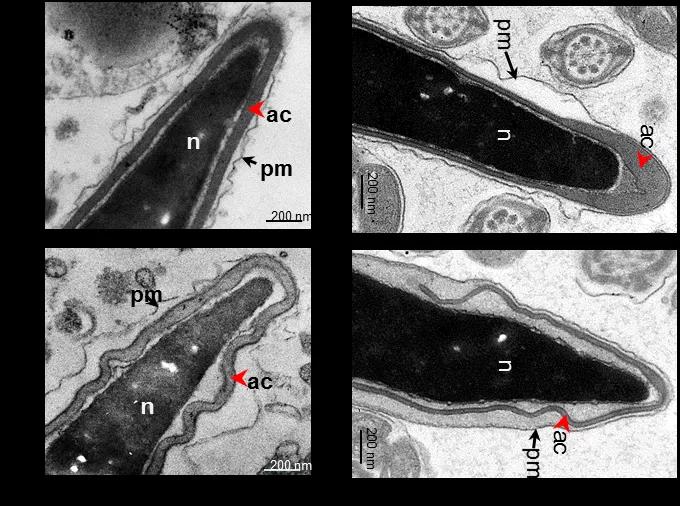

研究人员遂利用基因编辑技术建立了与患者一致的Actl7a点突变小鼠模型,发现该基因的突变不影响雄性小鼠的精子密度、活力及生殖系统的发育,只表现为雄性不育。经透射电镜对精子进一步分析发现,患者和突变小鼠的精子顶体都呈现褶皱脱落的形式,无法贴合在精子细胞核膜上,表现为顶体超微结构缺陷(图2)。

图2 患者及点突变小鼠精子的超微结构